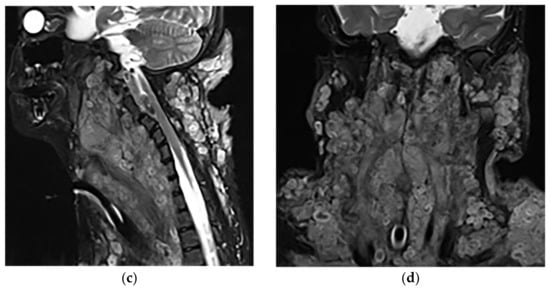

Figure 17.

A 34-year-old man, with a case of neurofibromatosis type 1. The axial T2W images (a,b) show multiple confluent infiltrative paraspinal masses within the neck and upper thorax along the course of sympathetic chain and nerves with high signal intensity and central focus of hypointensity (target sign) surrounding the mediastinal vessels that are typical for plexiform Neurofibroma. Sagittal T2W (c) and coronal (d) images show the extensive infiltrative nature of this lesion with multi-compartment involvement and extension to pharyngeal space and pressure effect over cervical and thoracic vertebrae.